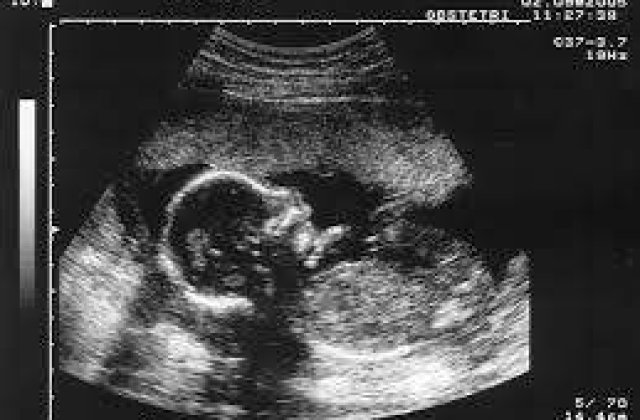

Femeia in varsta de 28 de ani a nascut noua dintre copii acasa si s-a deplasat la spital pentru a-l naste pe al 10-lea. Luni s-a dezvaluit ca toti cei 10 bebelusi au fost nascut morti. Decesele ar fi avut loc cand fetusii aveau doar 12 saptamani.

Se pare ca medicamentele pentru fertilitate au ajutat la conceptia neobisnuita a celor 10 copii. Doctorii care au tratat femeia au declarat ca uneori aceste medicamente au ca efect secundar hiperstimularea ovariana

"Se pare ca sarcina nu a mai fost urmarita dupa fertilizarea in Vitro. Cel putin trei copii puteau fi salvati daca sarcina era redusa", a declarat doctorul Sumitra Yadav.

Nadya Suleman detine recordul mondial pentru cei mai multi bebelusi nascuti care au supravietuit, record obtinut dupa ce a nascut opt copii in 2009.